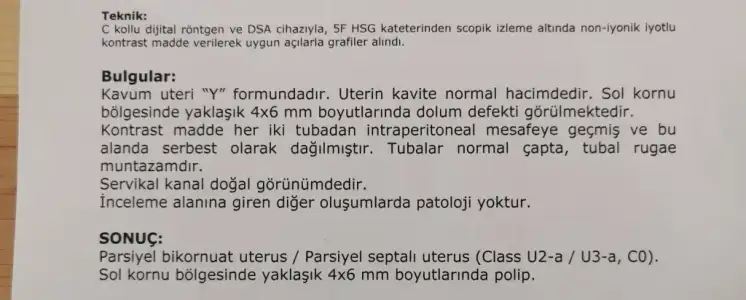

Selam canım, Ben 4 ay oldu Hsg çekildim ve anestesisiz çekildim hatta kendi tercihimdi. Doktor cekti.. Yani aslinda çok abartili bir agri sizi olmuuor ben dayandim ve bittikten sonra oyle yok yureyemiyorum yok agrim oluyor diye bir durumum da olmadi. Sayanabilecekcek hic korkma cektir.. Ultrason gibi alttan muayene gibi dusun. kisiden kisiye gore degisebilir tabiki fakat benim dayanilmayacak kadar acisi olmadi bi baslangicinsa hatta teki kapaliudi tupun acildi. Yani korkma derim kendini rahat birakirsan bol nefes alip verirsen hic bir sıkıntı olmaz korkulacak birsey yok

yeni tecrubem.. bende korkuyordum. anestezi olmadan daha iyi zaten. dayanirsin.